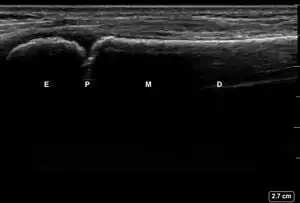

This module allows traditional bone setters, pre-hospital providers, clinical officers, nurses, nurse practitioners, and medical officers to become confident and competent in performing point-of-care ultrasound diagnostic imaging to rule out the presence of a pediatric distal forearm fracture and distinguish between buckle (torus) fractures and cortical break fractures to make appropriate referrals as part of the management of closed pediatric (< 16 years of age) distal forearm fractures in regions without access to X-ray imaging and orthopedic specialist coverage.[1][2][3][4][5][6][7][8][9]

Review all the acquired images to determine if they meet all the quality standards outlined in the checklist below.

| 5 | All features are properly labelled. | ![]() |